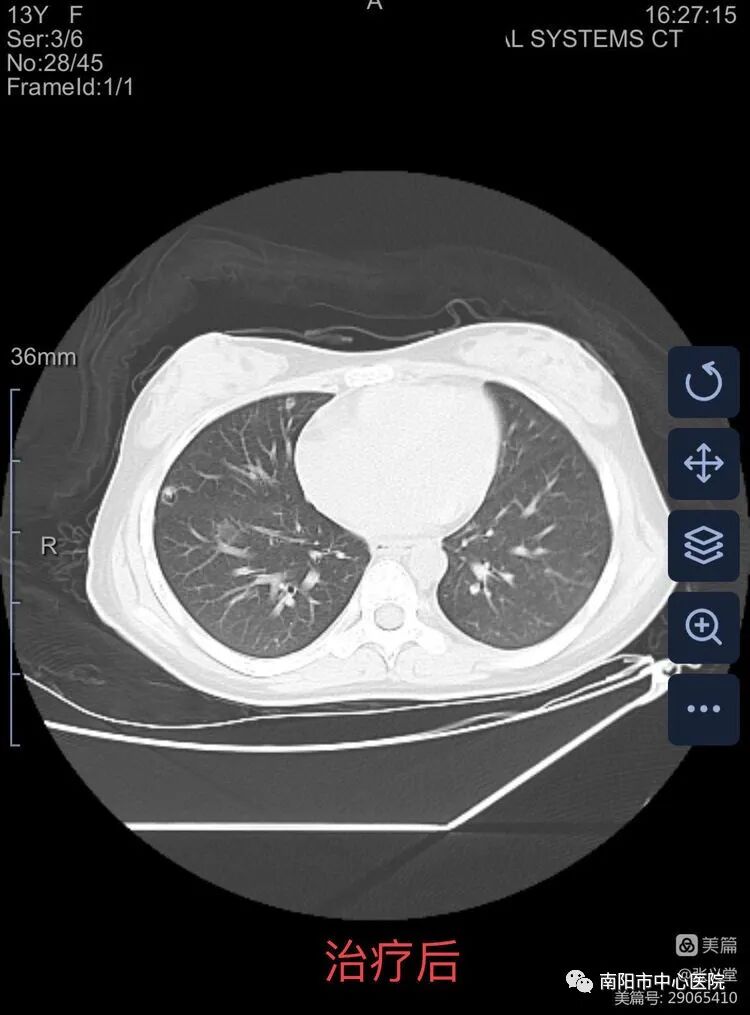

經(jīng)過全體醫(yī)護(hù)人員的精心治療,日夜的守護(hù),患兒酸中毒糾正,肺部感染控制,患兒意識轉(zhuǎn)清楚,5天后順利撤除呼吸機(jī),12天患兒尿量逐漸增多,腎功能逐步恢復(fù),精神好轉(zhuǎn),已經(jīng)能自主進(jìn)食,各項生命體征穩(wěn)定,已轉(zhuǎn)入兒童內(nèi)分泌??普{(diào)理控制血糖。 在搶救過程中,科室及時向家屬反饋患兒病情,取得了家屬的積極配合。患兒母親更是淚流滿面、激動地說:“多虧來到南陽市中心醫(yī)院兒童重癥醫(yī)學(xué)科,感謝你們及時診斷,準(zhǔn)確救治,救了我孩子一命!” 近年來兒童糖尿病發(fā)病有增多的趨勢,兒童糖尿病大多數(shù)為Ⅰ型糖尿病,大多數(shù)兒童因為昏迷酮癥酸中毒就診,酮癥酸中毒是兒童糖尿病臨床常見的危急并發(fā)癥及其最常見死亡原因。年齡越小,臨床癥狀越不典型,病情越重,臨床表現(xiàn)復(fù)雜多變,極易漏診或誤診,早期診斷,正確治療對救治至關(guān)重要。南陽市中心醫(yī)院兒童重癥醫(yī)學(xué)科開科以來成功救治過多例糖尿病酮癥酸中毒的患兒,具有較高的技術(shù)和豐富的臨床經(jīng)驗。此次患兒的成功救治,再次彰顯了兒童重癥醫(yī)學(xué)科在救治急危重癥病例的能力和技術(shù)水平。